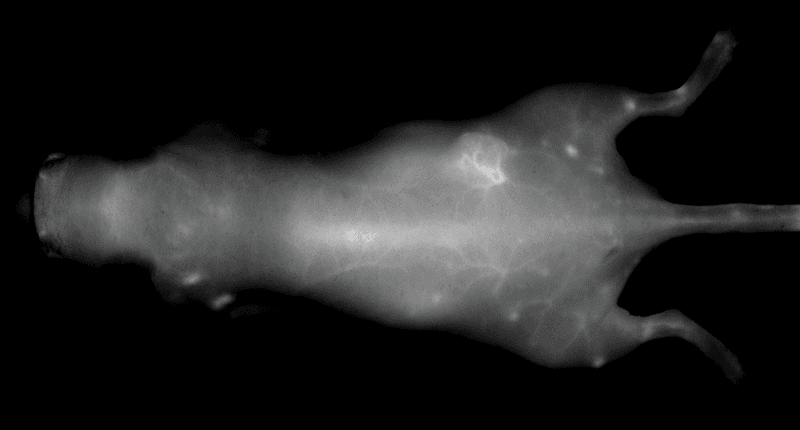

An NIR dye-conjugated contrast agent, such as IRDye 800CW PEG (polyethylene glycol), serves as a non-specific contrast agent for vascular imaging. The labeled agent is administered to mice intravenously (IV injection) and highlights surface vasculature for 30 minutes post-injection (Figure 6). The retention of the agent is visible in the tumor 4 hours post-injection (Figures 7A, B; requires appropriate mouse model*) and the tumor region is defined by 9 hours post-injection (Figure 8).

*Success of vascular imaging depends on the mouse model used. Vessels may be less visible in mice that are obese or have hair.